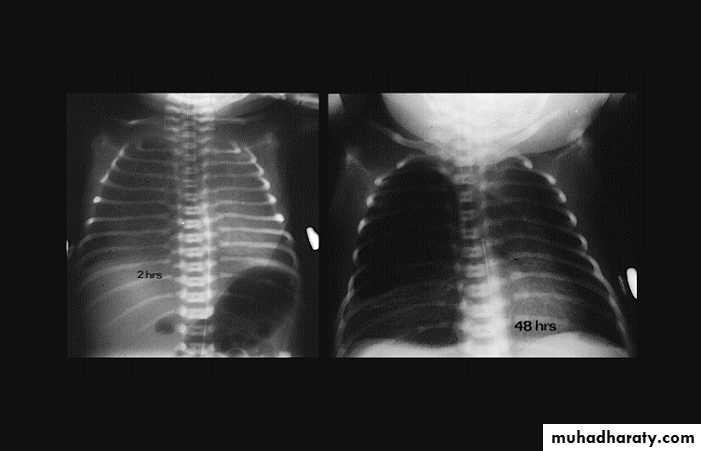

Congenital lober emphysema